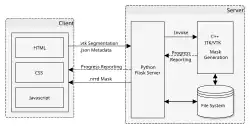

Architecture

Studierfenster is set up as a distributed application via a client–server model. The client side (front-end) consists of HTML and JavaScript with WebGL to enable 2D and 3D visualization, rendered on the client.

The server side (back-end) handles client requests via C, C++ and Python.[21] It interfaces to common open source libraries and software tools like the Insight Toolkit,[22] the Visualization Toolkit (VTK),[23] the X Toolkit (XTK)[24] and Slice:Drop.[25] The server communication is handled by AJAX requests[26] were needed.

Studierfenster employs a Flask server.